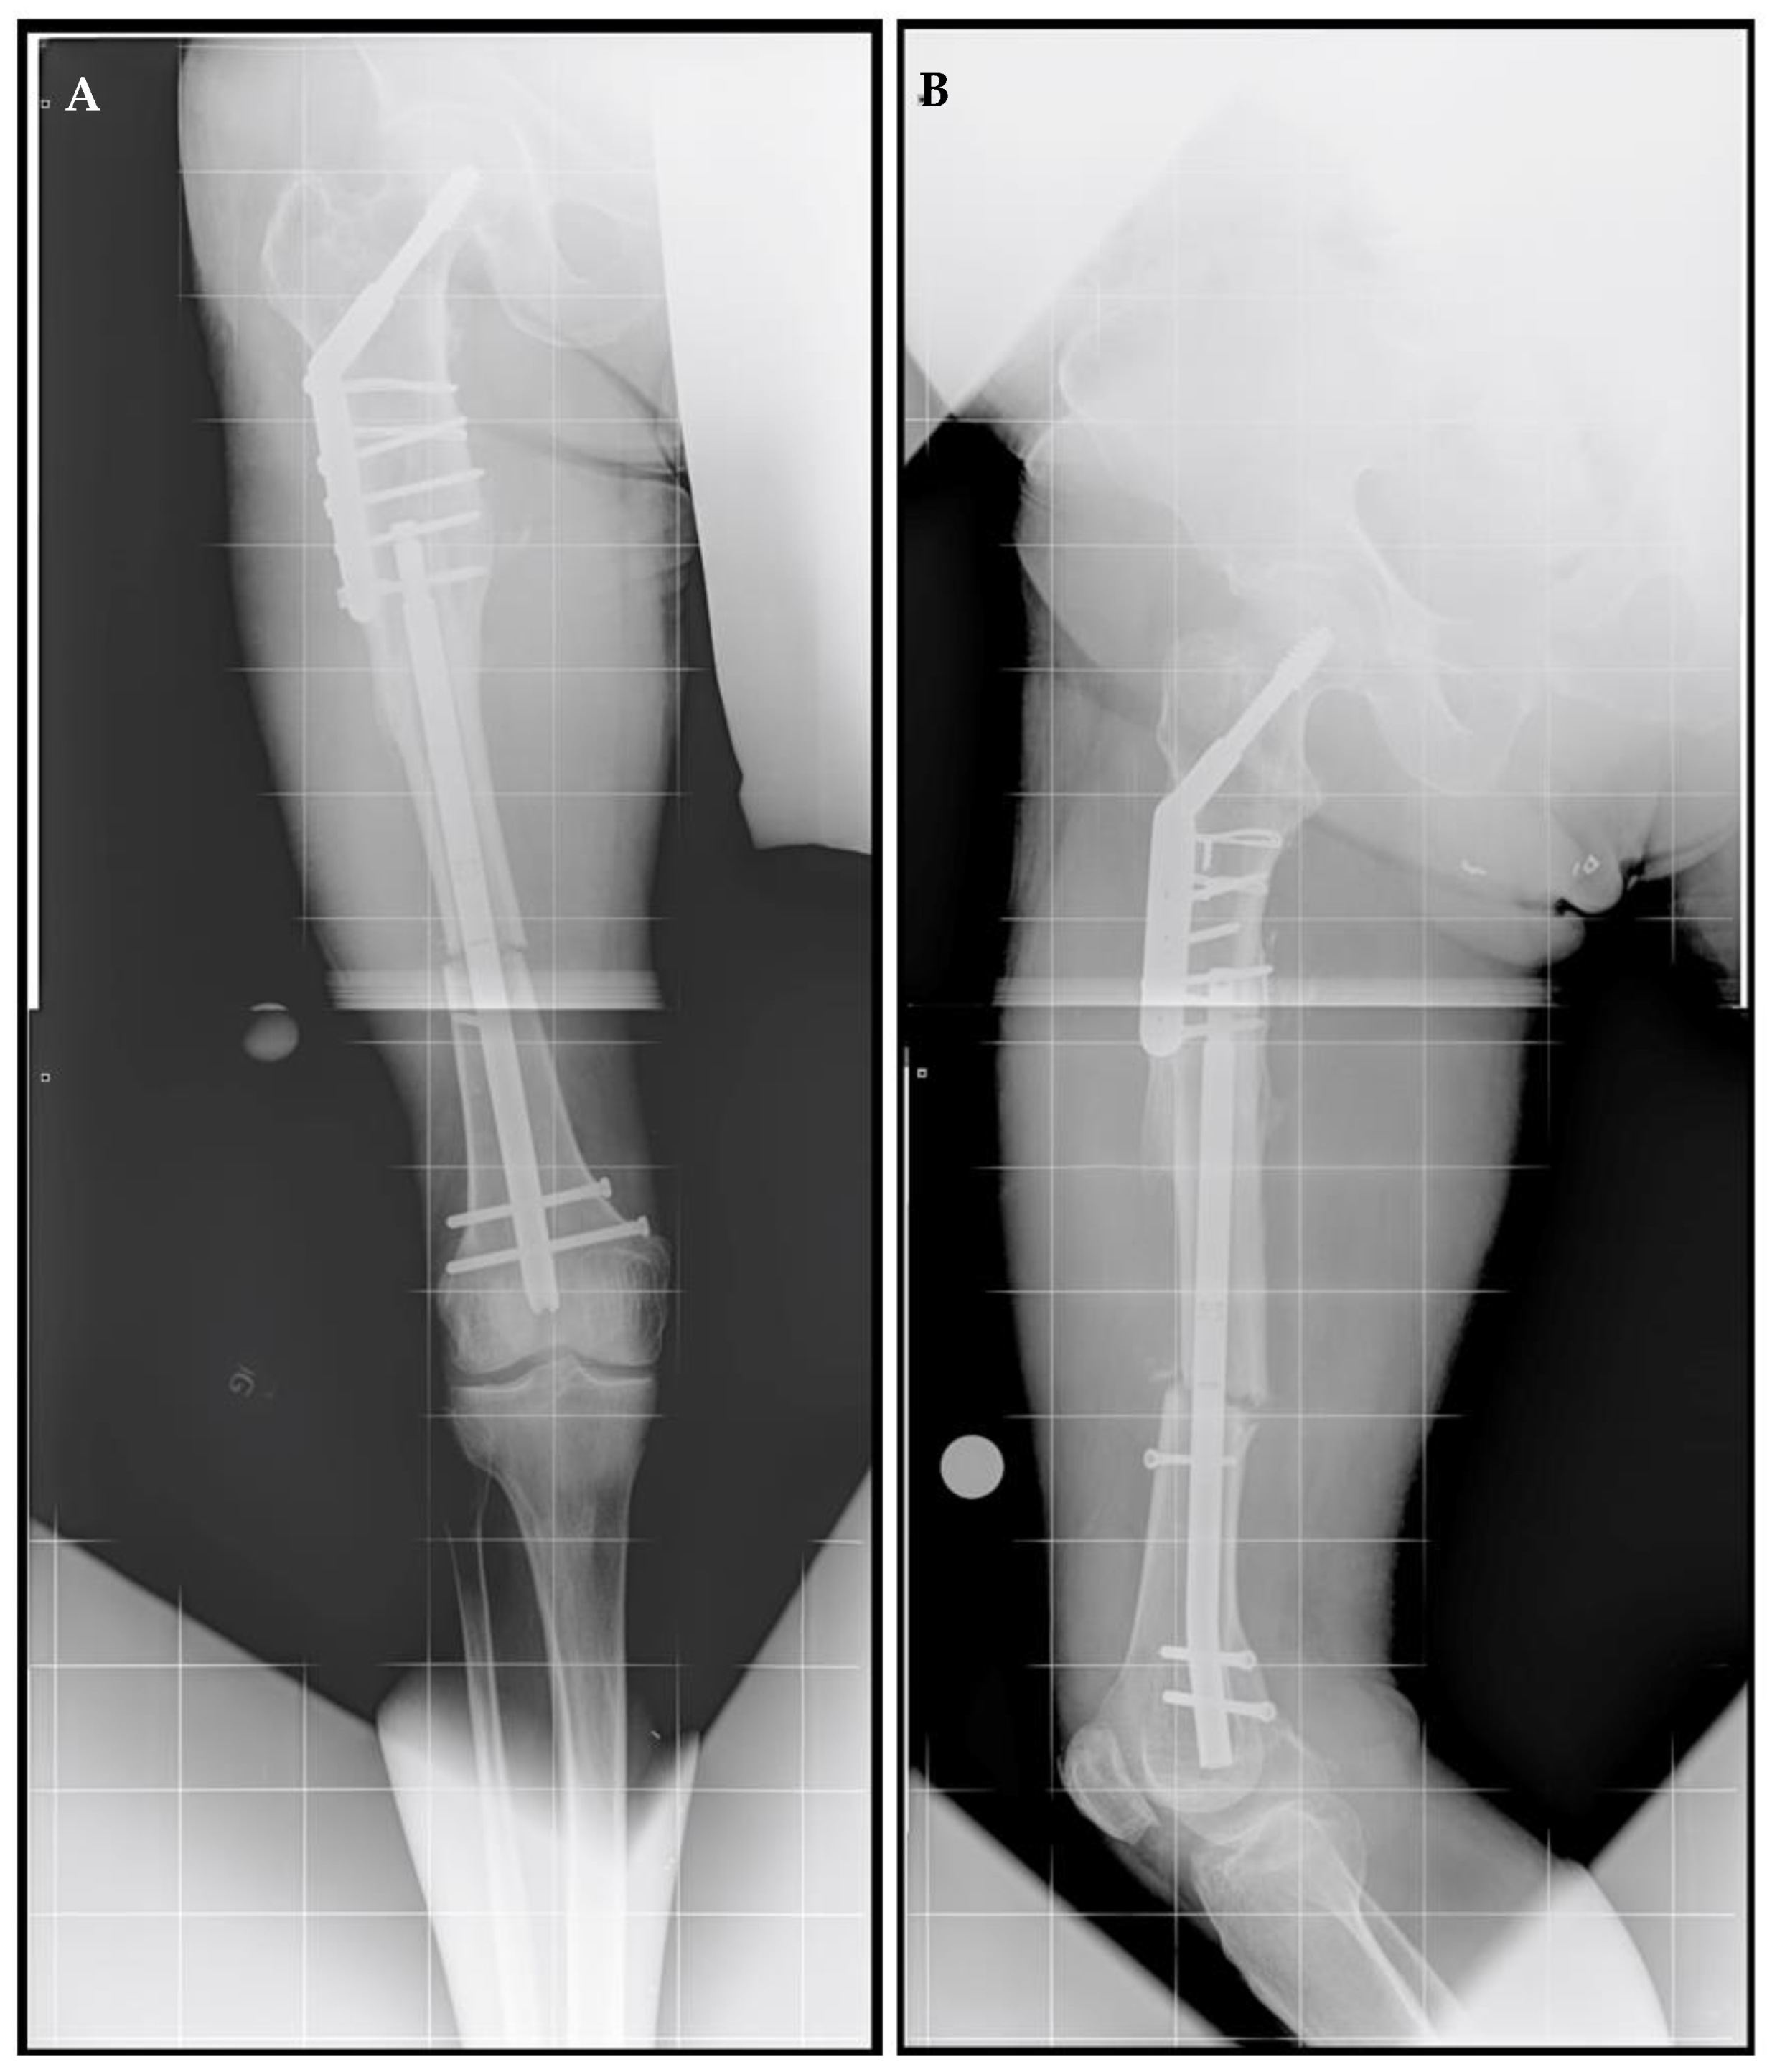

A right femoral osteoplasty was performed and a Precice MILN was inserted using the methods described above (Figure 2). The patient began lengthening as instructed on postoperative day five. He attended physical therapy and took vitamin D and calcium supplementation, as well as oxycodone as needed for pain management. Initial ROM of the knee joint was restricted from 0–50°, but full range was regained two months after surgery. He finished distraction 46 days after surgery (Figure 3). The patient completed consolidation 152 days after surgery and experienced no complications. At his latest follow-up appointment, his long leg films (Figure 4) demonstrated complete healing, remodeling, and equal limb length. The patient has returned to his active lifestyle, including skiing, and reported that he felt better on his bike and skis.

Figure 2.

Post-traumatic femoral lengthening in a 71-year-old male patient, shown here postoperatively. (A) Anteroposterior and (B) lateral of the right femur after osteoplasty and the insertion of the Precice MILN. Gray dots on the bottom represent X-ray calibration spheres.